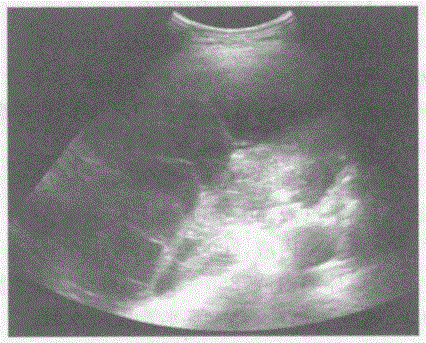

问题 临床资料:女,53岁,自述胸闷不适月余。 超声综合描述:左侧胸腔内可见大片状无回声区,呈网格状,最大深度4.8cm;其上方胸膜厚度1.1cm,边缘欠规整。 超声提示:

选项 A.左侧胸腔积液(内见分隔)左侧胸膜增厚 B.左侧胸腔包裹性积液 C.左膈下积液 D.左肺脓肿

答案 A